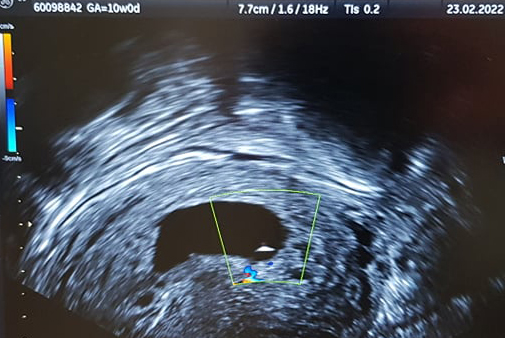

Falls jemand - warum auch immer - (fragt nicht, wonach ich die letzten Wochen gegoogelt habe... ... -.- ), das Bild sehen möchte, bittesehr, von gestern. rechnerisch 10+0, aber Embryoanlage 3 mm (quasi frühe Fehlgeburt, verhalten).

https://s20.directupload.net/images/220225/fvncd3i v.jpg